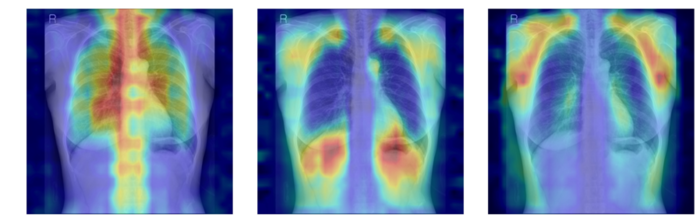

흉부 엑스레이에서 파운데이션 모델이 골다공증 판독을 위해 주목한 영역을 시각화한 이미지(사진=서울대병원) |

AI는 입력된 흉부 엑스레이에서 척추와 늑골 같은 뼈 구조를 중심으로 특징을 추출했다. 이를 기존 학습 패턴과 비교해 정상, 골감소증, 골다공증 중 어떤 상태와 가장 유사한지 판단했다.

연구팀은 여기에 더해 AI가 실제로 어떤 뼈를 근거로 삼아 판단하는지까지 확인할 수 있도록 '설명 가능성' 평가 체계를 설계했다. 뼈를 모두 가린 상태에서 특정 뼈 부위를 추가해 성능이 얼마나 향상하는지 확인하는 '차단 분석 방식'과 AI의 주목 영역이 실제 뼈 위치와 얼마나 일치하는지를 계산하는 '유의성 지도 방식'으로, AI가 임상적으로 중요한 뼈 구조를 근거로 판단하는지를 정량 검증했다.

연구 결과, DINOv2 모델에 LoRA 방식을 적용한 모델이 AUC 0.93으로 가장 높은 예측 성능을 보였다. 이 모델은 뼈 구조 활용도가 가장 높고, 주목 영역 타당성에서도 우수했다. 예측력과 설명 가능성이 균형 있게 확보된 최적 모델로 평가됐다.